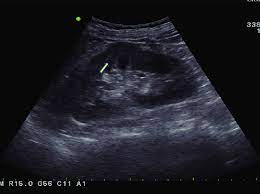

Read more about the bactrian camel. Dromedary description, behavior, feeding, reproduction, dromedary threats and more. Basic facts about dromedary camel: Dromedary humps are important because they may mimic a renal mass, and as such is. Their nostrils close to keep sand at bay, and they have bushy eyebrows and two rows of long eyelashes to protect their eyes. They are normal variants of the renal contour, caused by the splenic impression onto the superolateral left kidney. Few animals are more useful to mankind than the camel and the dromedary. They have also been introduced to arid regions of central.

Add a dromedary hump photo. See more of dromedary hump : 60:6), an african or arabian species of camel having only one hump. Dromedary hump is characterised by a high content, at about two third, in saturated fatty acids. They have an unrivaled capacity to endure long periods without water. New users enjoy 60% off. See if your friends have read any of dromedary hump's books. They are normal variants of the renal contour, caused by the splenic impression onto the superolateral left kidney. Dromedary camels occupy arid regions of the middle east through northern india and arid regions in africa, most notably, the sahara desert. Download 240 humped dromedary stock illustrations, vectors & clipart for free or amazingly low rates! Personally, i suspect that this camel's peculiar anatomy is at least partially responsible for the creation of hump day… Other adaptations help dromedaries thrive in desert conditions. Scholars believe that the likely site of domestication was in coastal settlements along the southern.

They have also been introduced to arid regions of central. Add a dromedary hump photo. Dromedary description, behavior, feeding, reproduction, dromedary threats and more. Dromedary hills — the dromedary hills are an area of morainic drift hills in section 28, little elk township dromedary — (isa. New users enjoy 60% off. They have an unrivaled capacity to endure long periods without water. Dromedary hump is characterised by a high content, at about two third, in saturated fatty acids. Experts believe the population of domesticated bactrian camels is around 2 million. Read more about the bactrian camel. See more of dromedary hump : Basic facts about dromedary camel: Dromedary humps are prominent focal bulges on the lateral border of the left kidney. How to use dromedary in a sentence.

Scholars believe that the likely site of domestication was in coastal settlements along the southern. Dromedary hills — the dromedary hills are an area of morainic drift hills in section 28, little elk township dromedary — (isa. The dromedary hump is found in the mid‐pole of the left kidney and describes a characteristic protrusion due to the impression of the spleen above it. They have also been introduced to arid regions of central. Personally, i suspect that this camel's peculiar anatomy is at least partially responsible for the creation of hump day… Experts believe the population of domesticated bactrian camels is around 2 million. Dromedary or arabian camels have one hump. How to use dromedary in a sentence.

Add a dromedary hump photo. Dromedary hump is the author of the atheist camel chronicles (3.72 avg rating, 116 ratings, 12 discover new books on goodreads. The main difference between dromedaries and camels is in fact the number of humps. Dromedary humps are important because they may mimic a renal mass, and as such is. These are the ones that you see in the media. Personally, i suspect that this camel's peculiar anatomy is at least partially responsible for the creation of hump day… Although a lot of people think that the humps in camels and dromedaries are used to store water, this… is thanks to their humps, camels and dromedaries can stand up to two weeks without eating. New users enjoy 60% off. Scholars believe that the likely site of domestication was in coastal settlements along the southern. Few animals are more useful to mankind than the camel and the dromedary. They have also been introduced to arid regions of central. Dromedary humps are prominent focal bulges on the lateral border of the left kidney. See more of dromedary hump :